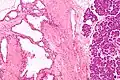

| Micrograph showing a pancreatic serous cystadenoma. H&E stain. | |

Pancreatic serous cystadenoma is a benign tumour of the pancreas.[2] It is usually solitary and found in the body or tail of the pancreas, and may be associated with von Hippel–Lindau syndrome.[2]

Pathologists classify serous cystic neoplasms into two broad groups. Those that are benign, that have not spread to other organs, are designated "serous cystadenoma".[5] Serous cystadenomas can be further sub-typed into microcystic, oligocystic (or macrocystic), solid, mixed serous-endocrine neoplasm, and VHL-associated serous cystic neoplasm. This latter classification scheme is useful because it highlights the range of appearances and the clinical associations of these neoplasms. Serous cystic neoplasms that have spread ("metastasized") to another organ are considered malignant and are designated "serous cystadenocarcinoma".

Pathology